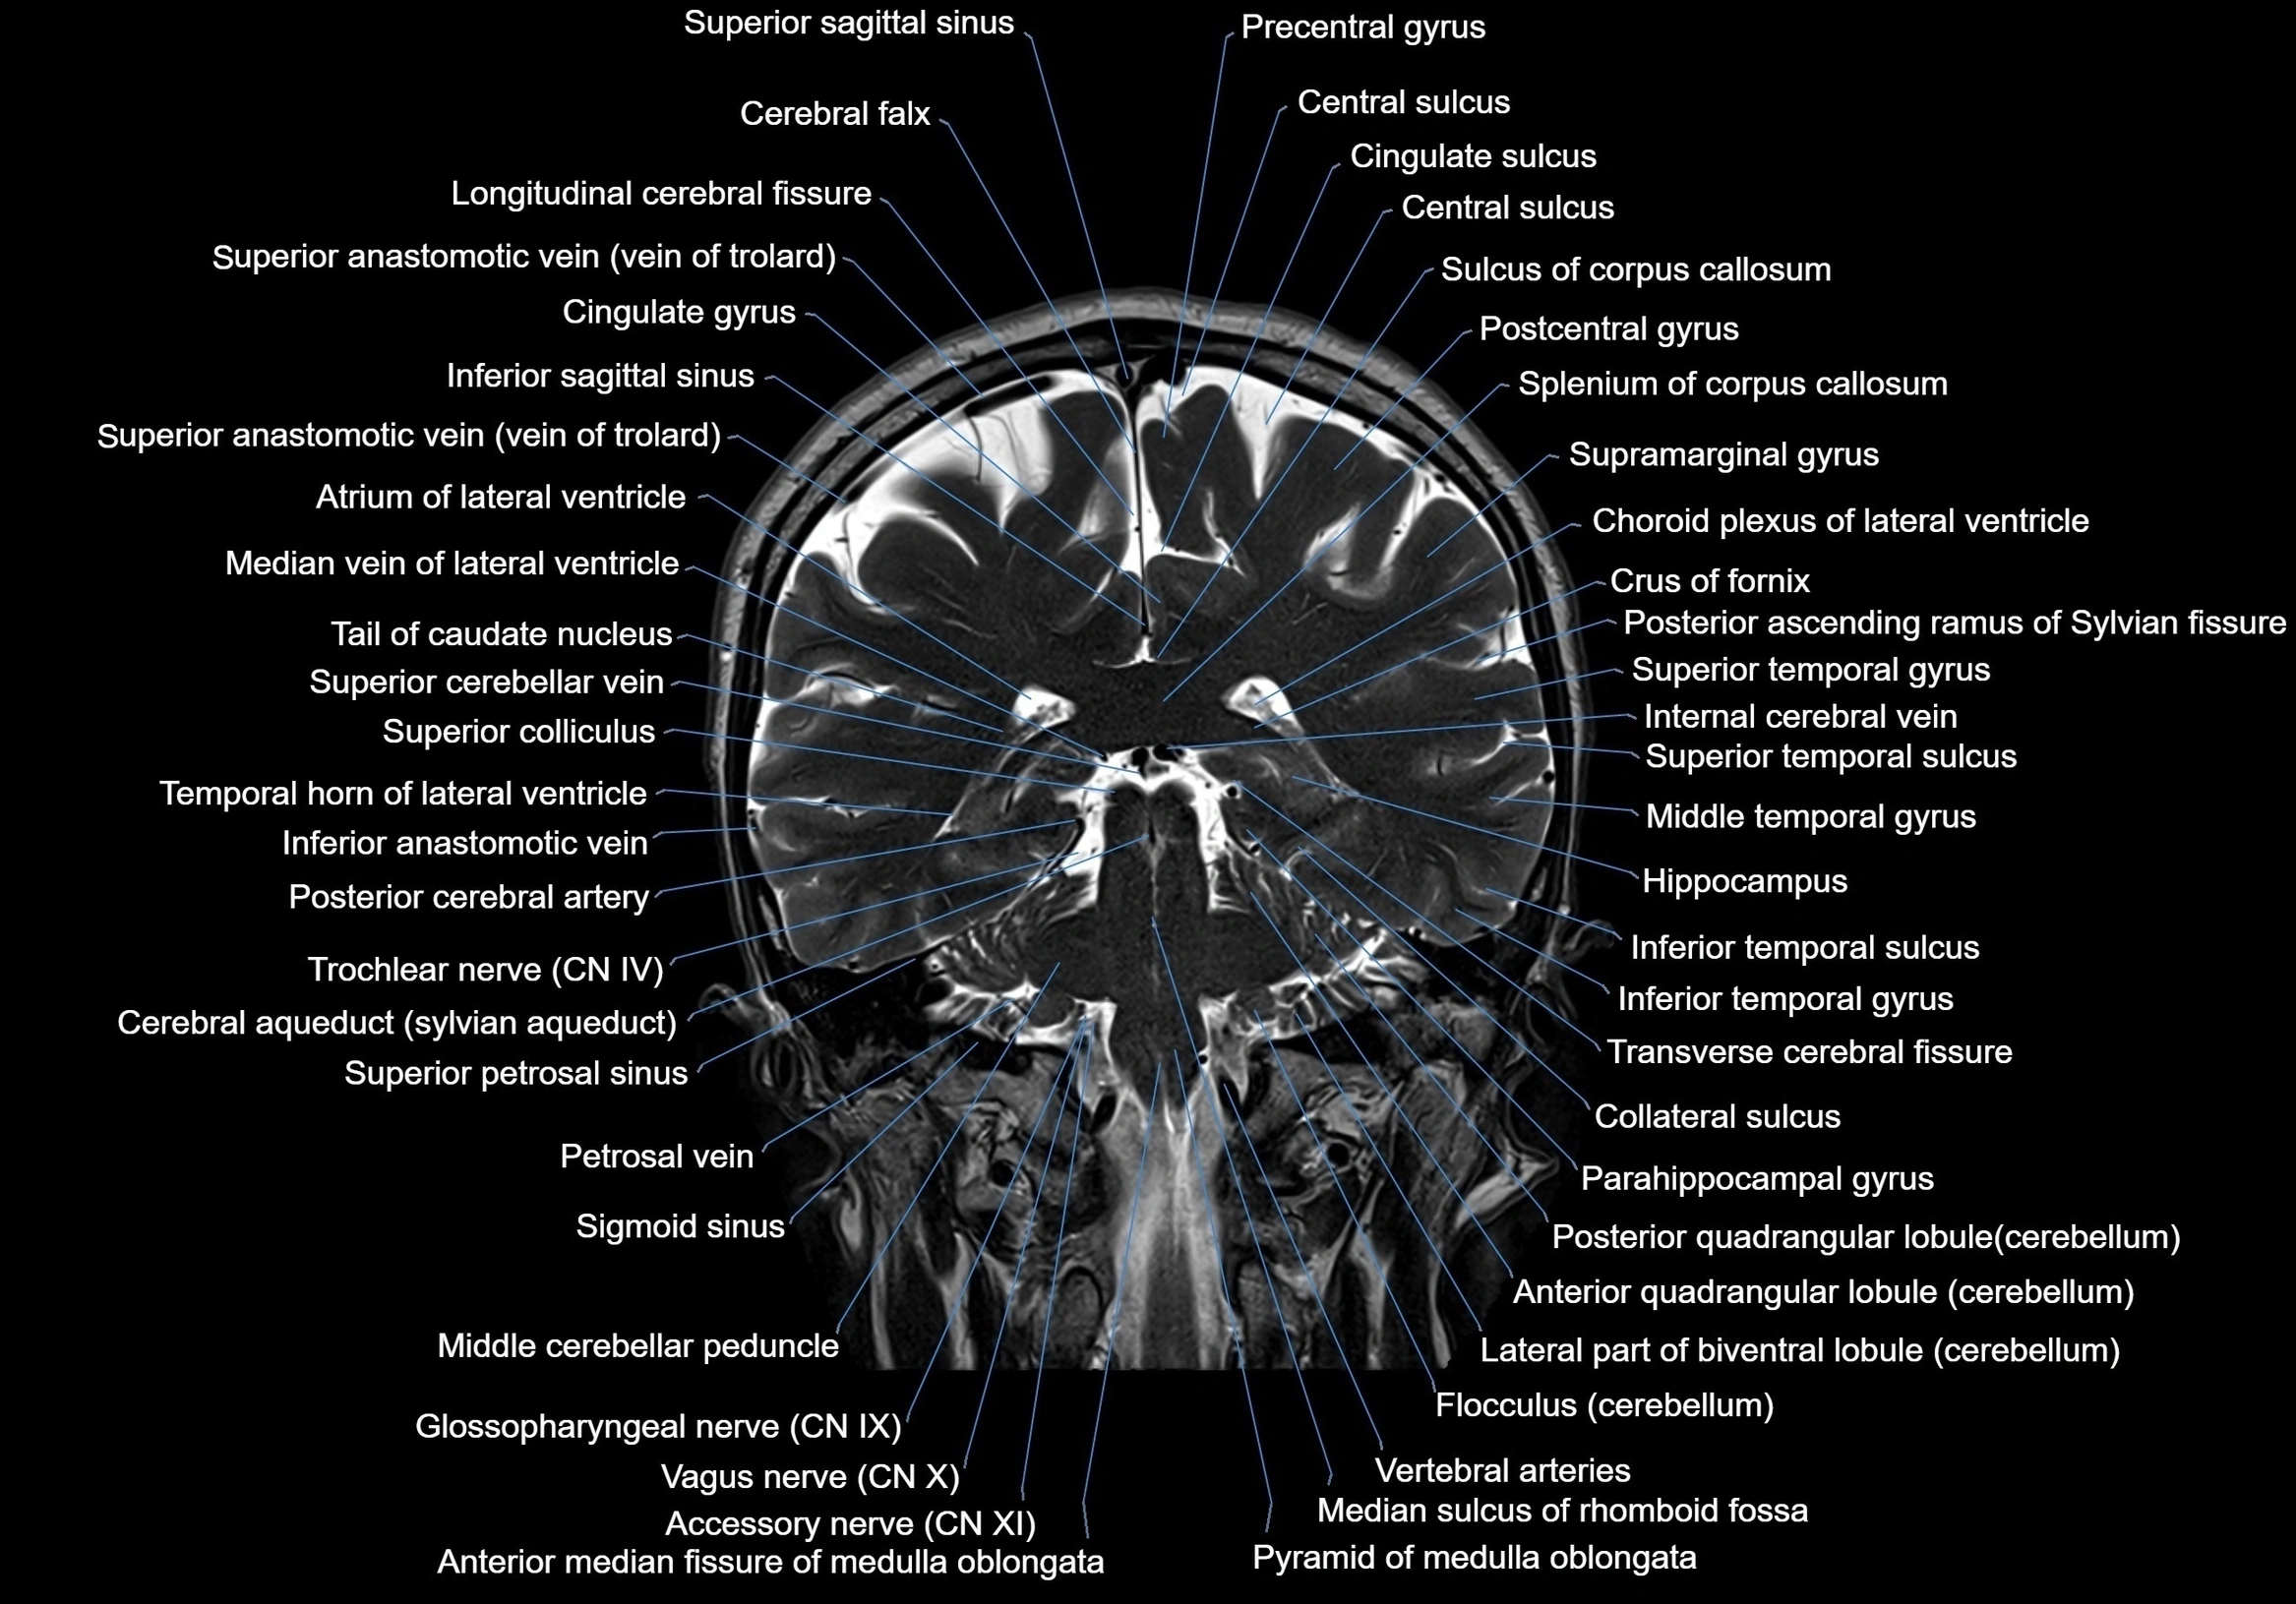

MRI images